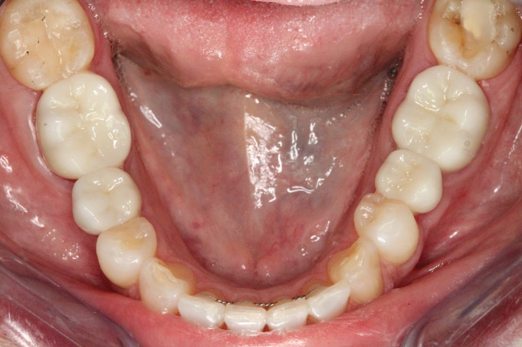

Fig 15. Provisionals 12 weeks postoperatively.

Figure 15

After the preparations were evaluated and accepted by the clinician, provisionals were completed with traditional crown-and-bridge techniques. Then the provisionals were fabricated with a replication stent derived from the diagnostic wax up (Figure 14). The provisionals were well-fitted to both the natural dentition and the ceramic dental implants (Figure 15). The provisional that was fixed to the implant was kept out of occlusion and had a narrow buccal-lingual occlusal table. The smaller occlusal table and short occlusal scheme provided light loading forces and stimulated the bone tissuethe brain detects the stimuli and sends osteoblasts to the area to increase bone density surrounding the implant. The recommendation for the light-loading provisional phase was to have the patient function with the provisionals for 4 weeks.